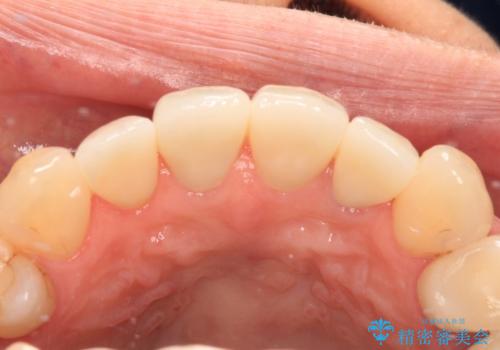

根管治療をしている歯もあるため、オールセラミッククラウンにすることとしました。

きれいに仕上がりとても満足されました。